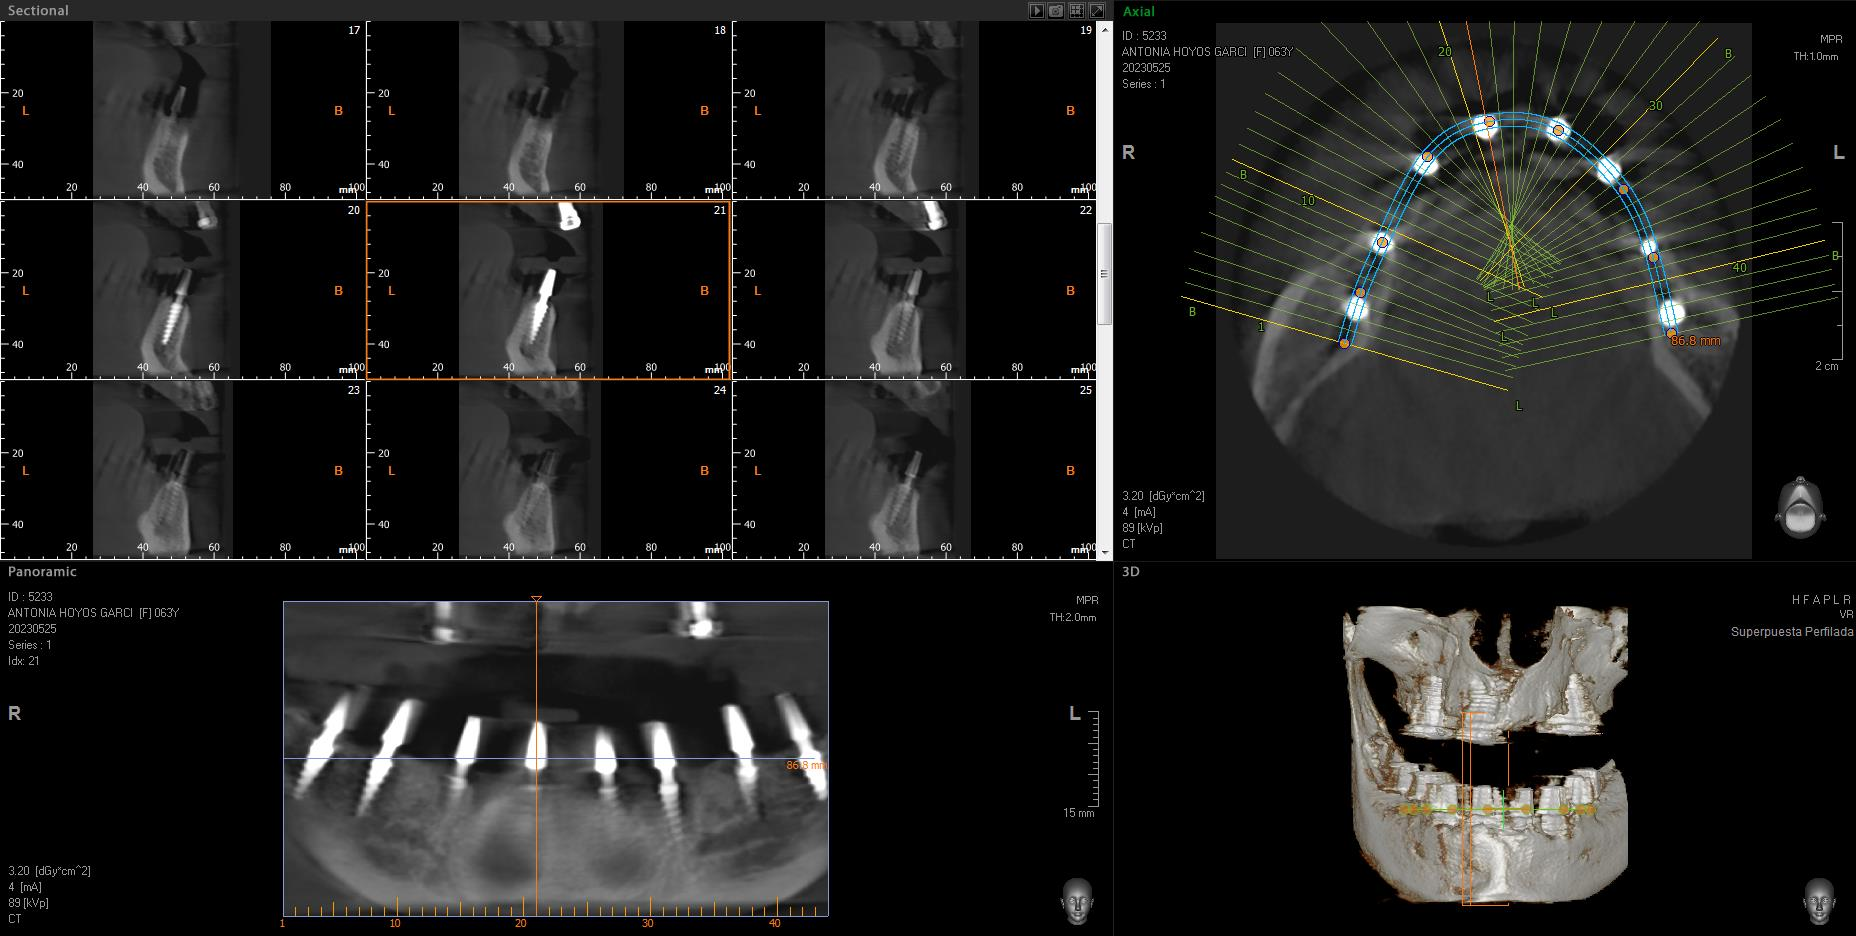

Implantes SLD-c

Secuencia de imágenes RX, antes y después de la inserción de implantes SLD-c en la parte inferior de la boca.

Paciente mujer de 65 años.

- Radiografía previa a la operación.

- Colocación implantes Radhex SLD-c parte inferior.

- Colocación implantes Radhex SLD-c parte inferior con soldadura.